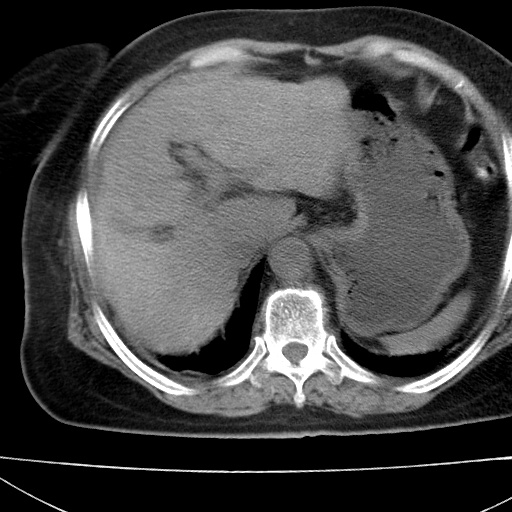

患者女74岁;右上腹胀痛1月,伴恶心,无发热;生活在疫水区。有术后病理及术后半年的追踪ct.

1)慢性血吸虫病(典型)。2)肝硬化。3)肝癌?4)胆囊炎。5)少量腹水。6)右侧少量胸腔积液。

支持.边缘见高密度线条样钙化影.

肝脏体积缩小,肝裂增宽,边缘不平呈波浪状,肝右叶见分隔状条索形钙化,亦见多结节低密度灶,边界不清,肝周可见少许液性暗区,胆囊增大内密度均匀,脾脏下缘低于脏脏的下缘,胸腔亦见液性暗区,余未见明显异常.

诊断:1肝硬化并慢性吸血虫病,脾肿大

2肝内占位,考虑肝癌可能性大,建议做增强

3胆囊炎, 4少量腹水及胸水

胆囊增大饱满,壁增厚。胆囊颈部见软组织密度影。临近肝右叶前段见片状低密度区,病灶下部见条状钙化,少量胸腹腔积液。意见:胆囊颈癌累及肝脏。

病人以胆囊癌手术的,病理结果为中分化腺癌。

现在看看肝右叶内圆形低密度影你们考虑什么呢?

肝内圆形低密度影考虑扩张的胆管

请看3mm重建像如下: